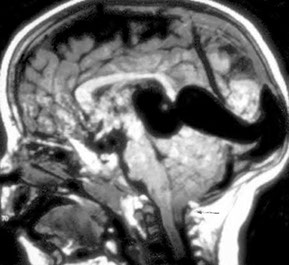

Aneurysm of the great vein of Galen can cause high output cardiac failure

Aneurysm of the Great Vein of Galen

Rare, congenital malformation of BVs that can cause High Output Cardiac Failure

- can present c developmental delay, hydrocephalus, seizure

- Great vein of Galen drains ant and central regions of brain into sinuses of posterior cerebral fossa